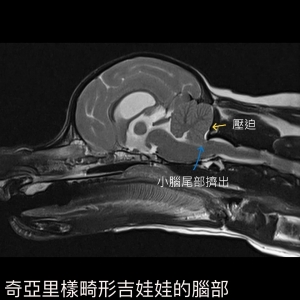

圖三為「奇亞里樣畸形吉娃娃的腦部」,小腦尾部擠出壓迫